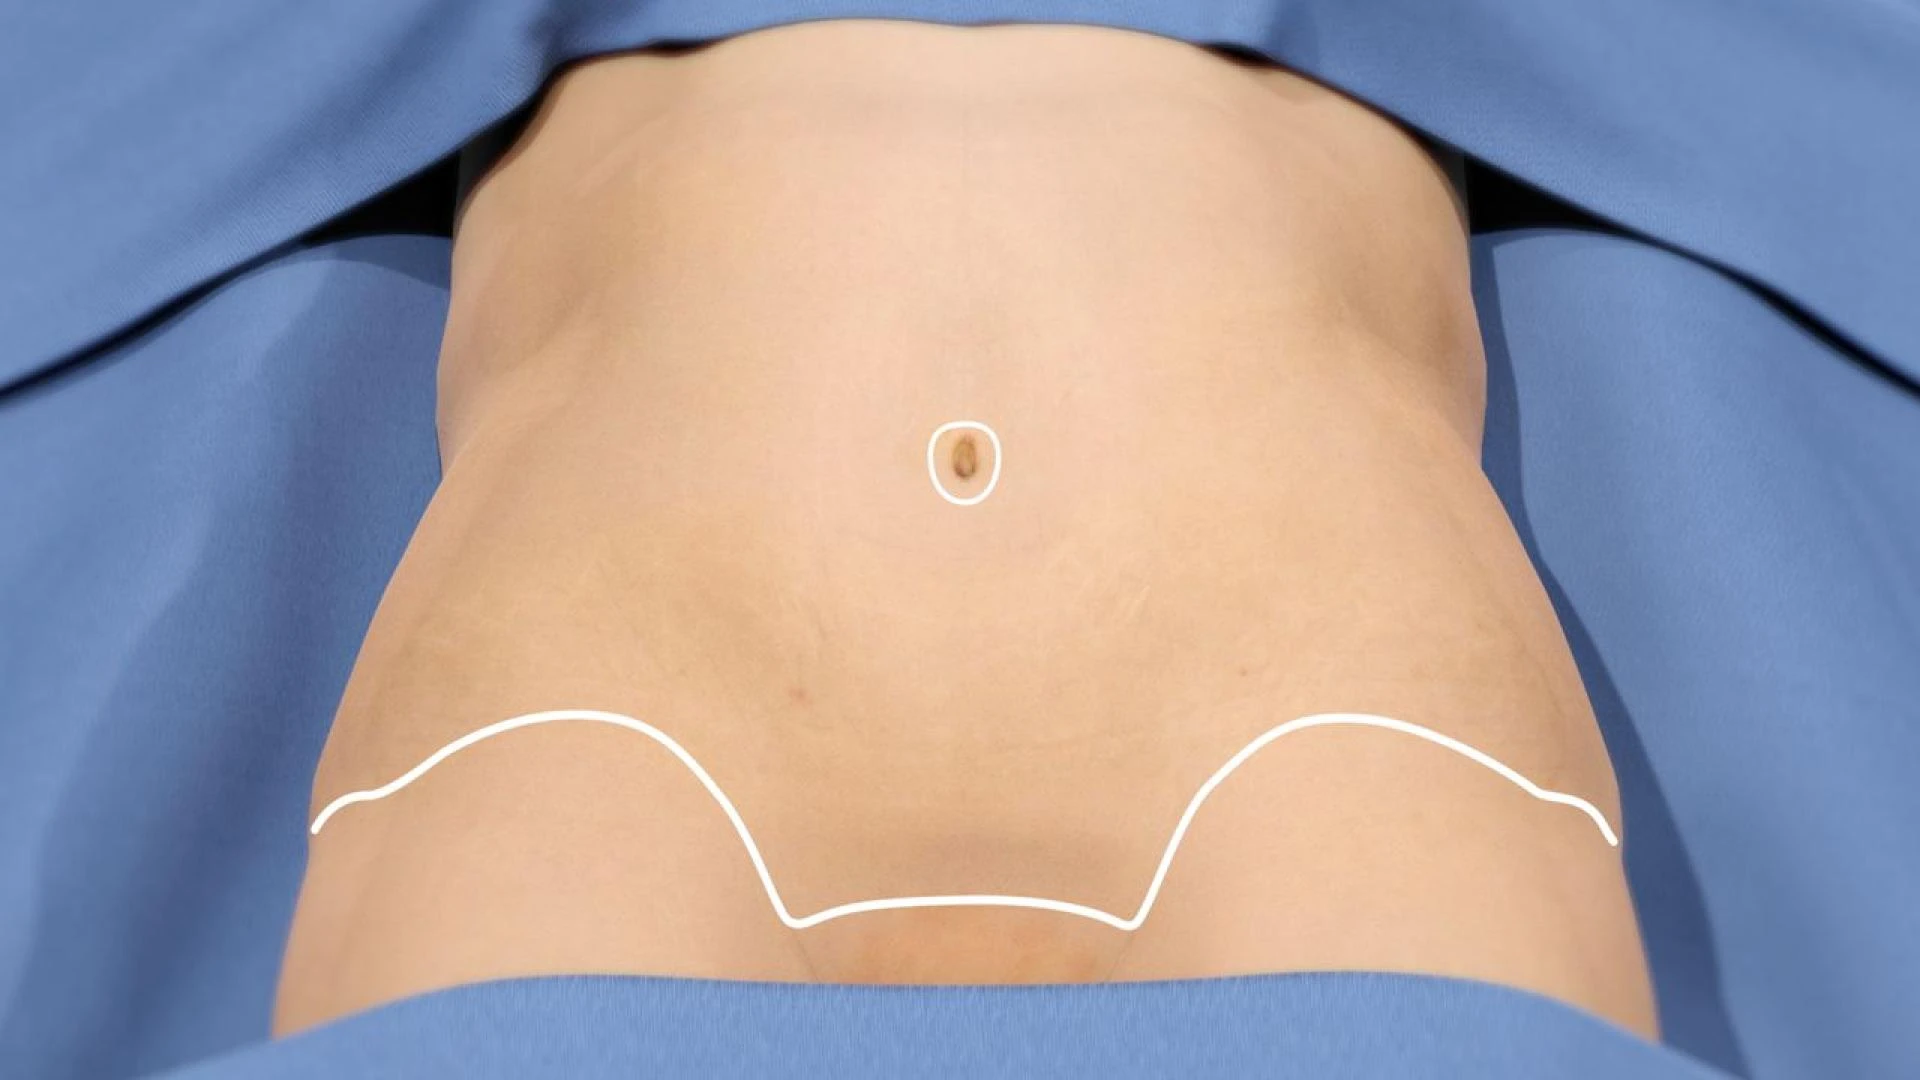

Where to Start When Considering a Tummy Tuck?

Where to Start When Considering a Tummy Tuck?